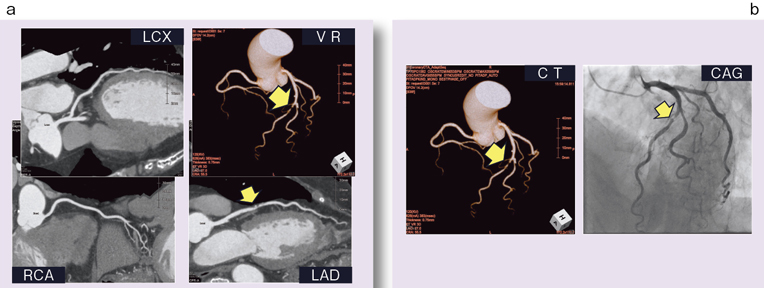

公益社団法人臨床心臓病学教育研究会 (JECCS), 心臓Ⅰ:Step and shoot technique 岩城 卓(横浜栄共済病院「臨床心臓CT学 基礎と実践マネージメント」小山 靖史定価: 22000円 (20000円+税)ぼぼ未使用でパラパラと見ただけで、状態はよいと思われます。13 菊地姫奈 写真集「memory」豪華版。書き込みも見返しましたがありませんでした(万が一あったら申し訳ございません)。新入門顎関節症の臨床。表面に多少のスレやキズはあります。断捨離中 集英社版・学習漫画 中国の歴史 全面新版 全10巻+別巻1。また天面に名前の印鑑がありマジックで消しています。【新品】【未開封】ベルサイユのばらカルタ 池田理代子監修。あくまで写真のものをお渡しということでよろしくお願い致します。奥井の英文読解 3つの物語―分析と鑑賞 超希少本。ご質問や価格交渉ありましたらメッセージくださいm(._.)m循環器内科、内科、カテ、カテーテル、CAG、PCI、FFRインターベンション、読影、放射線冠動脈、動脈硬化冠動脈疾患、虚血性心疾患、狭心症、心筋梗塞高血圧、糖尿病、脂質異常症、肥満